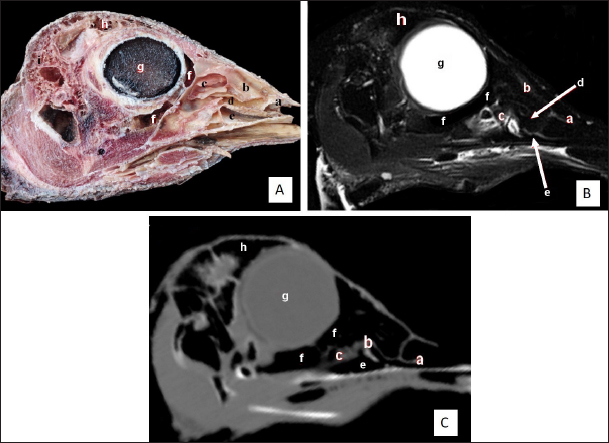

Fig. 2. Sagittal cross section of the adult ostrich head—level 1. A) Photograph of median sagittal anatomical section. B) MRI and C) computed tomography images showing: 1- Os premaxillare, 2- Culmen, 3- Nasal septum, 4- Os nasale, 5- Frontal sinus, 6- Frontal bone, 7- Cranial cavity, 8- Os parietale, 9- Os supraccipitale, 10- Os dentale, 11- Oral cavity, 12- Tongue, 13- Basihyoid, 14- Larynx, 15- Os basisphenoidale, 16- Vomer, and a- Optic lobe, b- Pons, c- Medulla oblongata, d- Cerebral hemisphere, e- Cerebellum, f- Optic chiasma and g- Pituitary gland.

Two featherless oval nostrils were found on either side of the premaxilla and covered by a characteristic operculum at the entrance. The upper beak’s dorsal ridge (culmen) was located between both nostrils (Fig. 1A and B). The nasal cavity was cone-shaped, extending to reach the choanae. Dorsolateral bony boundaries of the nasal cavity are the frontal process of the premaxilla, nasal, and dorsal horizontal plate of ethmoidal and nasal bone’s lateral process, while the ventral boundary created by the maxillary and palatine processes of the premaxilla, maxilla, and rostral part of the pterygoid and vomer bones. The vomer bone was pneumatic. The nasal septum divides the nasal cavity into two halves and consists of caudal bony and rostral cartilaginous parts (Fig. 2).

There are three types of nasal conchae: rostral, middle, and caudal (Figs. 35). The rostral nasal concha extended to reach the middle third of the nasal cavity (Fig. 3), and it was partially visible through the nostrils (Fig. 1B). The cross-section showed a T-shaped projection linked to the nasal cavity’s lateral wall, forming dorsal and ventral recesses. The rostral concha extends caudally beneath the rostral section of the middle nasal concha, forming the middle nasal meatus. At the floor of the nasal cavity, there is a feature mucous membrane fold connecting the rostral concha to the nasal septum (Fig. 6).

The middle nasal concha was more prominent than the rostral concha. It was situated on the caudo-dorsally to rostral one and resembled a coiled or bulla-shaped structure. The middle nasal concha was located in the middle of the nasal cavity, between the dorsal and middle nasal meatus (Figs. 3,4,5,6D, and 7A).

The caudal nasal concha is the smallest triangular one. In cross-section, it appeared scroll-like, attached rostrally to the middle one, making it difficult to differentiate between them. While caudally, the ventral nasal meatus was connected to the infraorbital sinus and the oropharyngeal cavity by two slits (or holes) in the palate called choanae.

The nasal conchae exhibited in the MRI images as bright (high or hyperintense signal intensity) to gray (low or hypointense signal intensity) structures that could be divided into three parts: rostral, middle, and caudal conchae, which correlated to the morphological examinations. In contrast, the nasal conchae could not be recognized clearly on CT images compared to those obtained after MRI (Figs. 25 B and C). The paranasal sinuses with other structures could be identified using both CT and MRI. The nasal septum and paranasal sinuses revealed a white bone border (high signal intensity), soft tissue was grey (low-to-intermediate signal intensity), and they contained black gas, so both the CT and MRI scans showed little signal intensity (Figs. 15B and C and 79B, C, E, F).